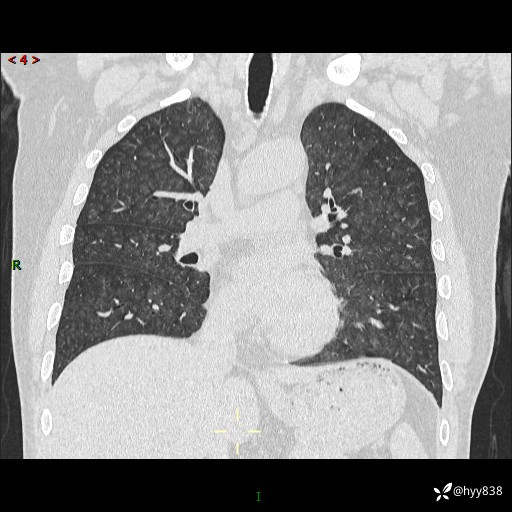

辅助检查:CT

胸部HRCT